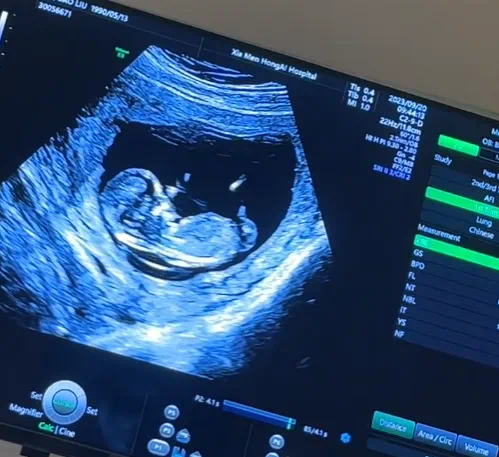

nt检查是孕妈妈在怀孕11到14周之间需要去医院做的一项重要排畸检查,医学上称为颈项透明层扫描。这项检查的主要目的是排查胎儿是否存在畸形问题,不过,在民间,却流传着一些通过nt检查来判断胎儿性别的说法。

有一种说法是,如果nt值大于1.5,那么肚子里是男孩的可能性较大;而当nt值小于1时,女孩的可能性更大。不过,当nt值处于1-1.4之间,就难以准确判断胎儿性别了,男孩女孩都有可能。已生宝妈们解释说,这是因为男孩的皮肤要比女孩的皮肤厚一些,所以nt值会相对高一些。但需要注意的是,一般正常的nt值都在3mm以下。

从nt图的形状也能判断胎儿性别?有人认为,如果nt图显示的是弯曲的形状,那腹中胎儿通常是男孩;要是nt图呈现平行的状态,一般就是女孩。

通过nt单上宝宝身上的亮点判断生男生女,是比较常见的一种说法。很多已经生了孩子的宝妈分享经验称,当nt单显示3个亮点的时候,大概率会生儿子;如果显示的不是亮点而是直线,就会生女儿。

另外,从nub点的位置和形态也能推测胎儿性别。nub点如果和脊柱线的位置呈现的角度大于30度,证明会生男孩;nub点如果和脊柱线的位置呈现的角度小于30度,则暗示生女孩。还有,如果nub点上翘,屁股也微微上翘,后背脊柱成圆弧状,也暗示生男孩;如果nub点比较平,脊背也比较平,则暗示生女孩。